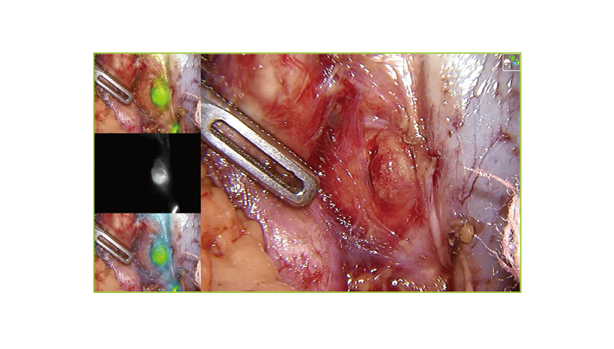

同時顯示白光模式、是非熒光模式及熒光

融合模式的畫面;;;;;;;;

在不影響白光模式下手術操作的同時,,,,,,,,

展示熒光劑顯影位置,,,,,,,,有用實現術中熒光導航。。。。。。。。